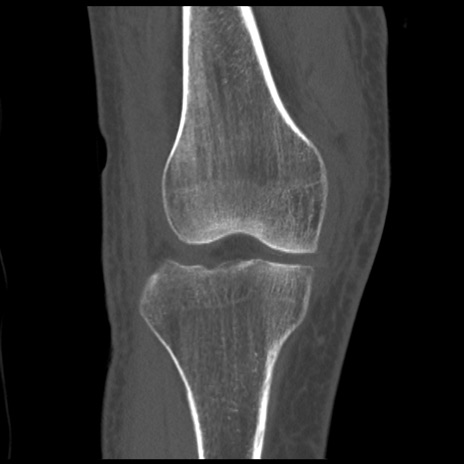

右膝関節CT